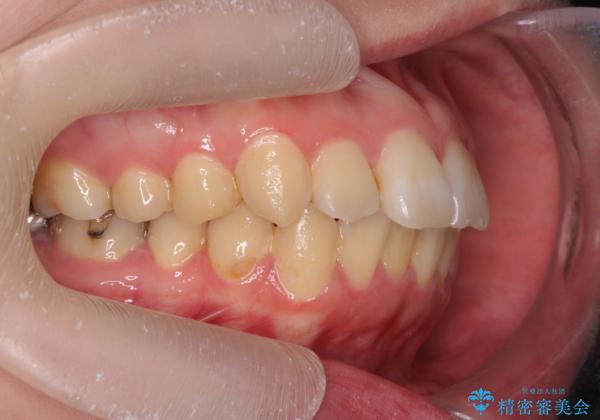

- 歯を抜かずに前歯の角度を改善したい、と矯正治療を希望され来院されました。

可及的に前歯部にIPR(歯間の削合)を行い、抜歯をせずマウスピース矯正システムインビザラインで歯の排列を行っていく治療計画としました。

治療の前後を比べると、がたつきや歯の角度が改善したことがしっかりと確認されました。